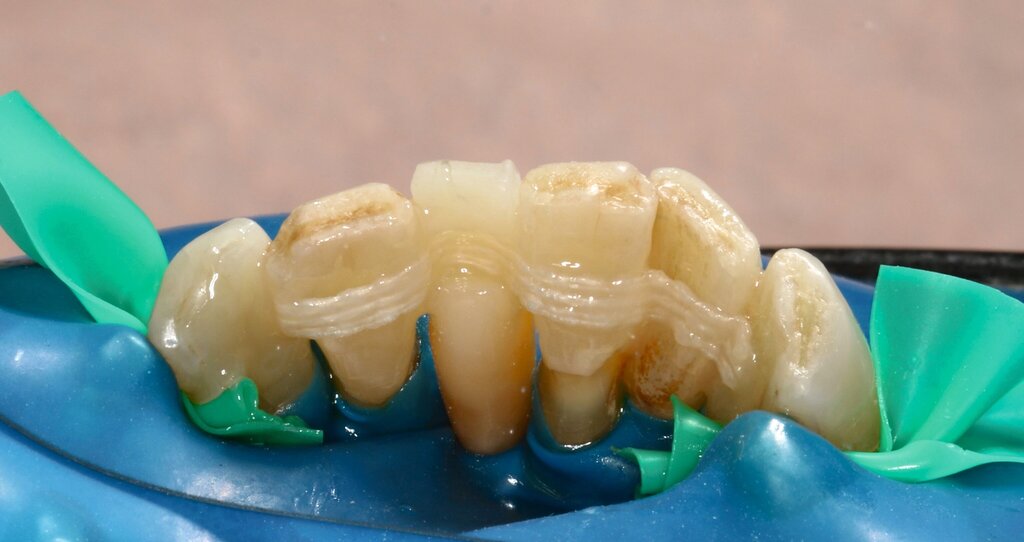

Anschließend wurde die unpräparierte Zahnoberfläche mittels 35-prozentiger Phosphorsäure (Ultra Etch, Ultradent) 60 Sekunden lang geätzt, mit einem Zwei-Komponenten-Adhäsivsystem (Optibond FL, Kerr) vorbereitet und das zur Schienung verwendete Polyethylenband (Ribbond THM Adhäsiv Verstärkungsband, Ribbond Inc.) mit Komposit (CeramX Spectra STHV & ST flow, Dentsply Sirona) fixiert. Die Polyethylenband-Oberfläche wurde großzügig mit Komposit überdeckt, ebenso wurden die Zähne mittels Komposit deutlich verblockt, um eine möglichst hohe Stabilität der Schienung zu erreichen. Gleichzeitig wurde weiterhin darauf geachtet, dass die Hygienefähigkeit der Interdentalräume erhalten bleibt (Abbildung 10).